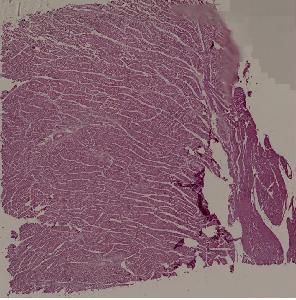

8. Granulation tissue